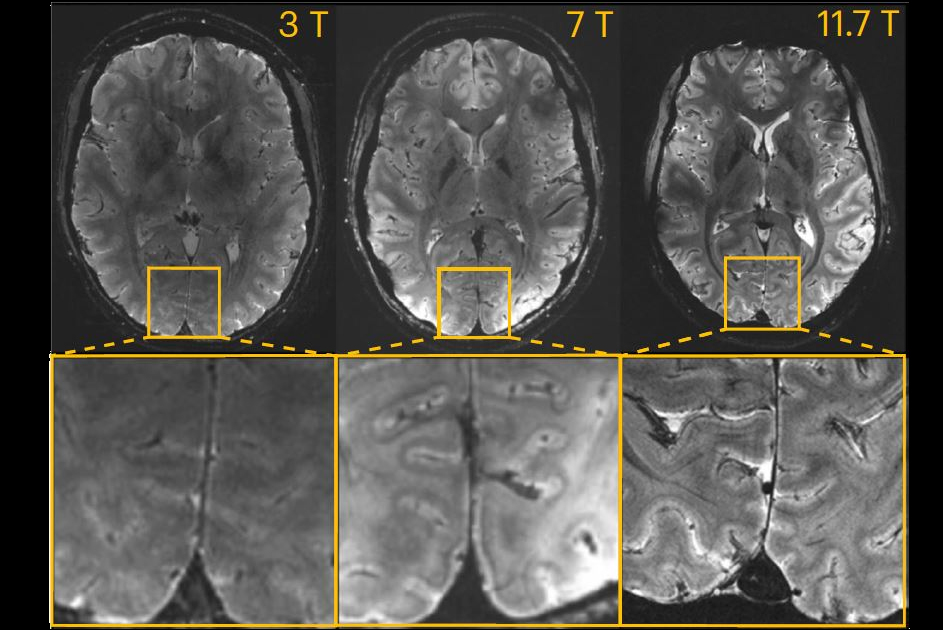

"We should consider this outstanding instrument as a prototype," he said. "We are in a similar situation as with astronomy. Using fancy telescopes, one may discover new stars, planets. But, once we know where to look, more modest instruments would work as well.

"We hope that what we find or discover with our 11.7 tesla system may then be visible on lower field (7 tesla, 3 tesla) systems; this is MRI translational research in some way."